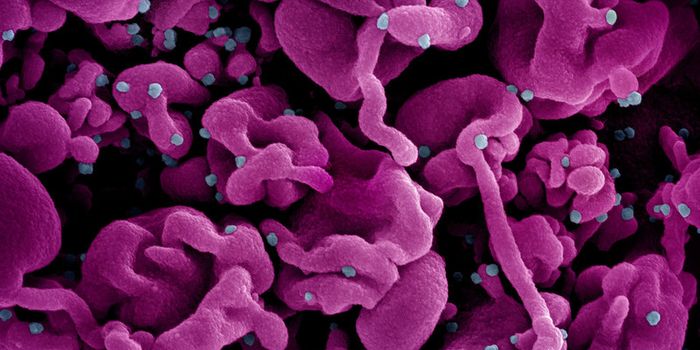

FEB 04, 2025Clinical & Molecular DXSudan virus (SUDV) can infect people to cause Sudan virus disease (SVD). Right now, an outbreak of SVD has been detected ...